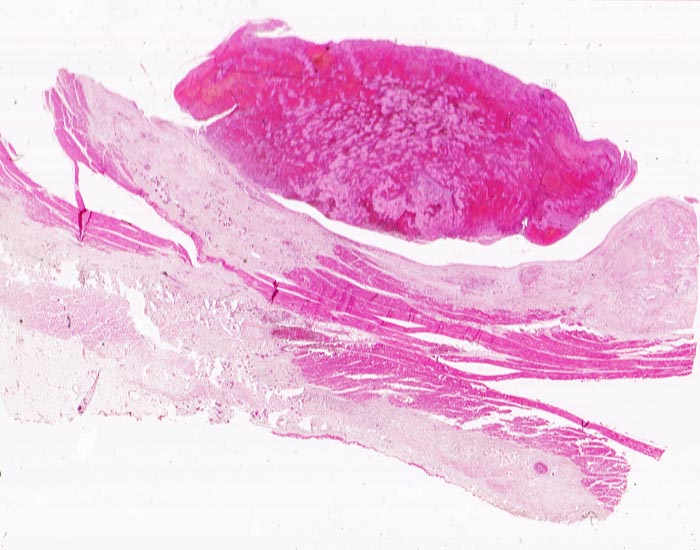

PathoPic ID 4567 - Transmuraler Myokardinfarkt mit Parietalthrombose

Transmuraler Myokardinfarkt mit Parietalthrombose

vaskulär / Durchblutungsstörung

Herz links

Kardiovaskuläres System

Hypereosinophiles nekrotisches

Myokard. Dem Endokard zum Ventrikellumen hin anhaftender geschichteter Thrombus. Dünne

Fibrinschicht auf dem Epikard.

Diagnose eines Myokardinfarktes vor 4 Tagen.

Histologie

Scan

75